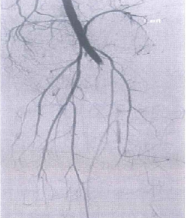

- Chụp mạch là biện pháp hiệu quả để chẩn đoán xác định tổn thương mạch máu trong trật khớp gối, chỉ định trong các trường hợp lâm sàng còn tưới máu tốt nhưng chỉ số ABI < 0,85.

Hình 10.2. Tổn thương mạch khoeo trong trật khớp gối